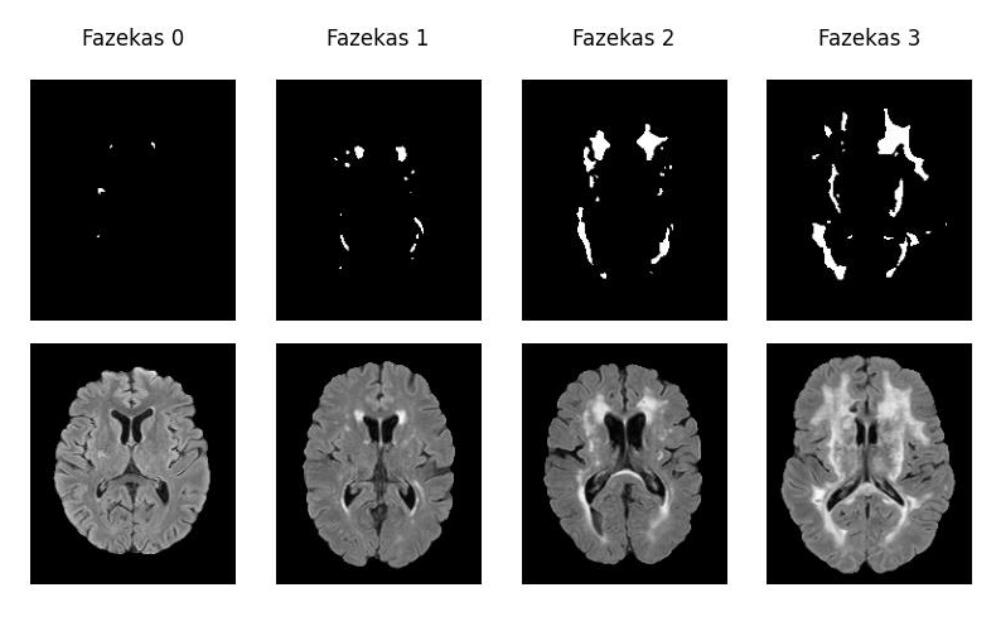

White Matter Hyperintensities

quantification